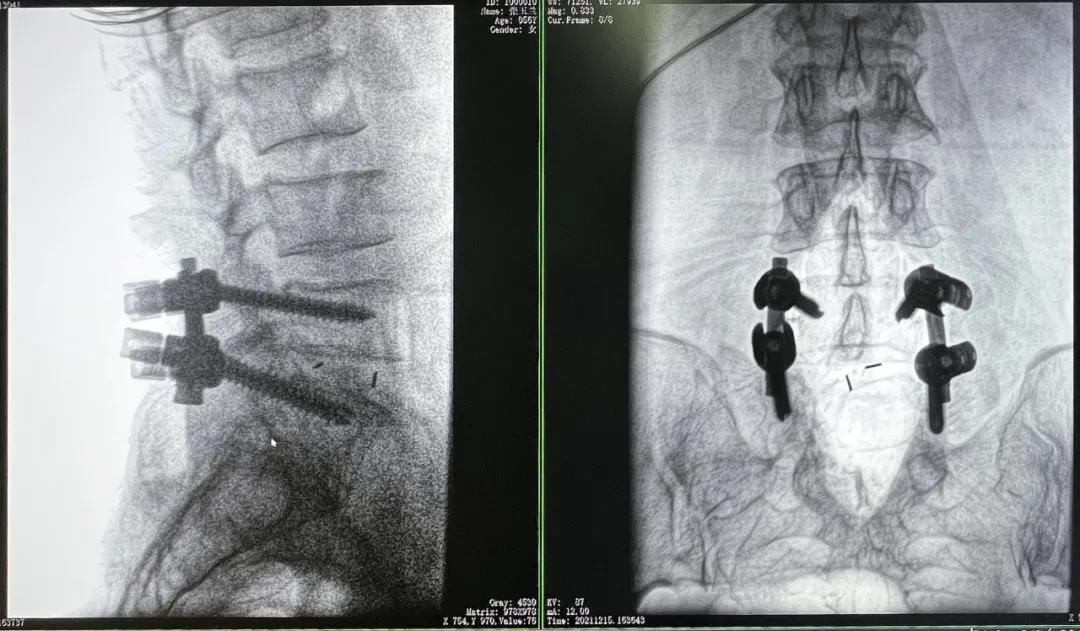

患者1:女性,56岁,L5/S1椎间盘椎板减压+钉棒固定术

患者下腰部疼痛,活动受限,伴有左下肢疼痛5年,久站或弯腰干活时疼痛加剧,卧床休息后疼痛症状缓解,近一个月情况加重,需行椎板减压+钉棒固定术。

3D C形臂摆位及手术前二维影像

医生在影像引导下在L5/S1椎弓根处打入医用螺钉

术中快速生成横断面、矢状面、冠状面断层图像和三维立体图像